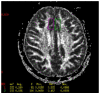

Schizophrenia is characterized by complex metabolic dysregulations and their consequences. Until now, numerous theories have explained its pathogenesis, using a spectrum of available technologies. We focused our interest on lipid profile-periphery high-density cholesterol level and lipoproteins in the human brain and compared magnetic resonance imaging (MRI) scans of patients with schizophrenia and the healthy group. Detailed analysis of biochemical parameters was performed using magnetic resonance spectroscopy. Our study aimed to reveal correlations between periphery high-density lipoproteins levels and lipoproteins in the brain, depicted in MRI scans, and parameters of peripheral oxidative stress expressed as paraoxonase. Patients with schizophrenia have decreased levels of high-density lipoproteins, low paraoxonase activity, and slightly raised sodium in the blood. Positive significant correlations between serum high-density cholesterol and anterior cingulate cortex, unique brain area for schizophrenia pathophysiology, MR spectroscopy signals, and diffusion have been revealed. To our knowledge, this is the first study to describe the effect of an anterior cingulate disorder on high-density cholesterol levels on the development of schizophrenia.